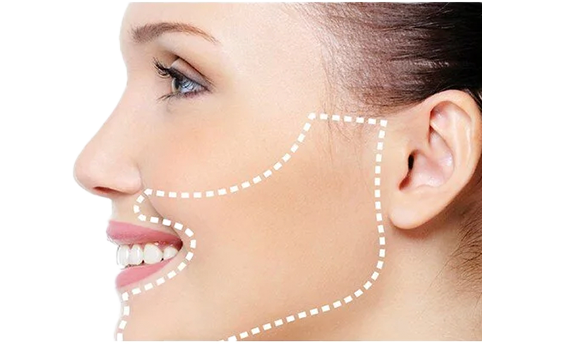

Ortognatik Cerrahi; Çift Çene Cerrahisi olarak da bilinen bu cerrahi müdaheleler, çene kemiklerindeki deformiteleri (düzensizlik) düzeltir ve çiğneme fonksiyonunu optimize etmek için çeneleri ve dişleri yeniden hizalamayı kapsar. Bu düzeltmeleri yapmak genellikle estetik olarak yüz görünümünü iyileştirir.

Ameliyat genellikle inra- oral (ağzı içi) yapılır, bu nedenle çene veya ağız çevresinde herhangi bir ameliyat izi görülmez. Ancak bazen extra –oral (ağız dış) küçük kesiler gerekebilir.

Çene ameliyatı üst çene, alt çene, çene ucu ( genioplasty) veya bunların herhangi bir kombinasyonu ile yapılır.